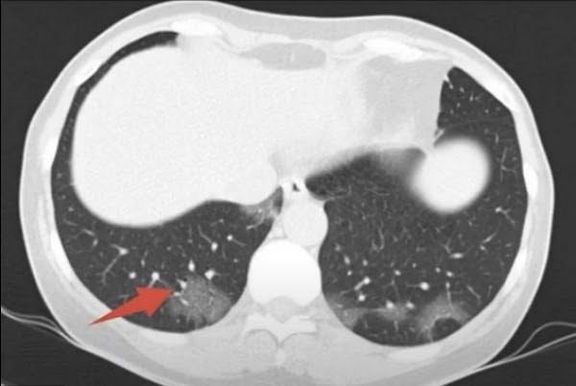

Для пневмонии при COVID-19 характерно двустороннее поражение легких, поэтому врач по результатам томографии также оценивают тяжесть заболевания. Для этого разработана эмпирическая шкала визуальной оценки легких, в которой КТ-0, КТ-1, КТ-2, КТ-3 и КТ-4 соответствуют стадии заболевания и, соответственно, степени поражения легких.

Если в это время сделать КТ легких, на полученных снимках будут видны обусловленные вирусным поражением двусторонние изменения в легких в виде затемнений округлой формы, склонных сливаться между собой и формировать так называемый рентгенологический признак «эффект матового стекла». После разрешения воспалительного процесса, отмершие участки легких заменяются фиброзными рубцами. Рентген не дает такой исчерпывающей информации, как КТ, и в легких ситуациях при незначительном объеме поражений легких может вовсе оказаться бесполезным, так как изменения не будут видны.